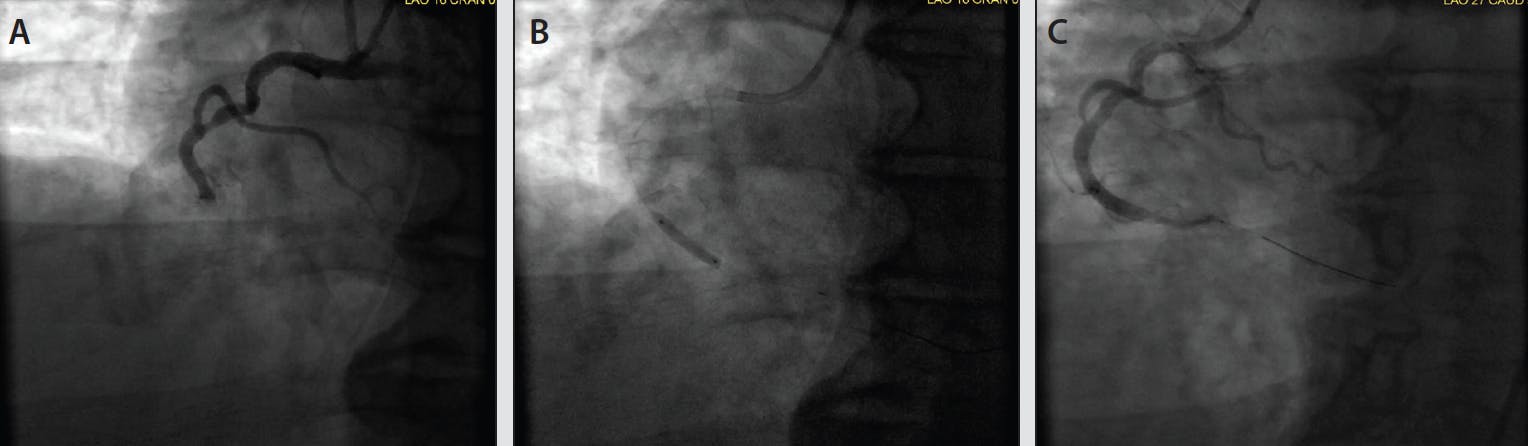

Figure 4 and Figure 5 showcase two cases from our experience that demonstrate the benefit of frontline utilization of CAT RX. In the first case (Figure 4), balloon angioplasty was used prior to CAT RX. Distal embolization caused by the initial balloon inflation potentially limited the ability to achieve TIMI 3 flow. In the second case (Figure 5), CAT RX was used frontline. After one pass of CAT RX there was clear visualization of the underlying lesion, a stent was placed, and TIMI 3 flow was achieved with myocardial perfusion normalization.

Figure 4. A male patient in his mid 50s presenting with acute thrombotic occlusion of the right coronary artery (A). Initial balloon inflation with 2- X 15-mm balloon (B). Final result showing distal embolization caused by initial balloon angioplasty, potentially limiting the ability to achieve TIMI 3 flow (C).